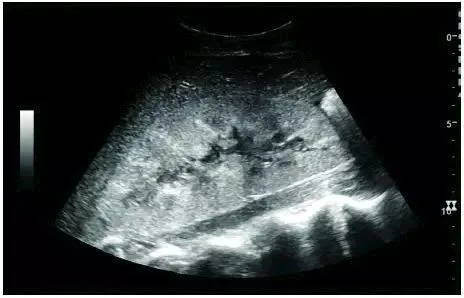

Longitudinal scan with an ultrasound probe showed that the kidney was broad bean-shaped, and the right kidney was lower than the left kidney; the left kidney showed a single hump because it was close to the spleen. The kidney can be divided into the renal parenchyma and the renal sinus; the renal sinus is hyperechoic on ultrasound imaging and the renal parenchyma is hypoechoic: this can be divided into an outer cortical area and an inner medullary area (cone echo). Between the medulla is the renal column.

Normal adult kidney ultrasound scan image: *renal column, **renal pyramid, ***renal cortex, ****renal sinus